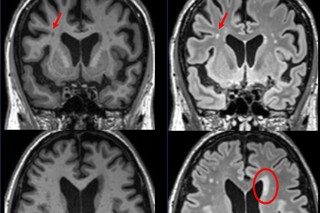

Four brain scans

The connection between cell dysfunction and delirium

IADRC expert, Sophia Wang, MD, received a grant from the National Institute on Aging to explore an area of the COVID-19 pandemic that connects endothelial cell dysfunction with intensive care unit (ICU) patients who develop delirium.